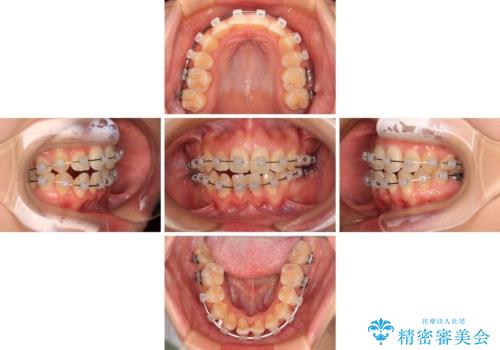

- クリアブラケット

- 治療期間

- 1年

- 治療回数

- 10-30回